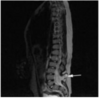

What pathology does this depict? [1]

Placenta praevia Fig 3 – Anterior placenta previa. The placenta (arrow) has covered the internal os completely (arrowhead).